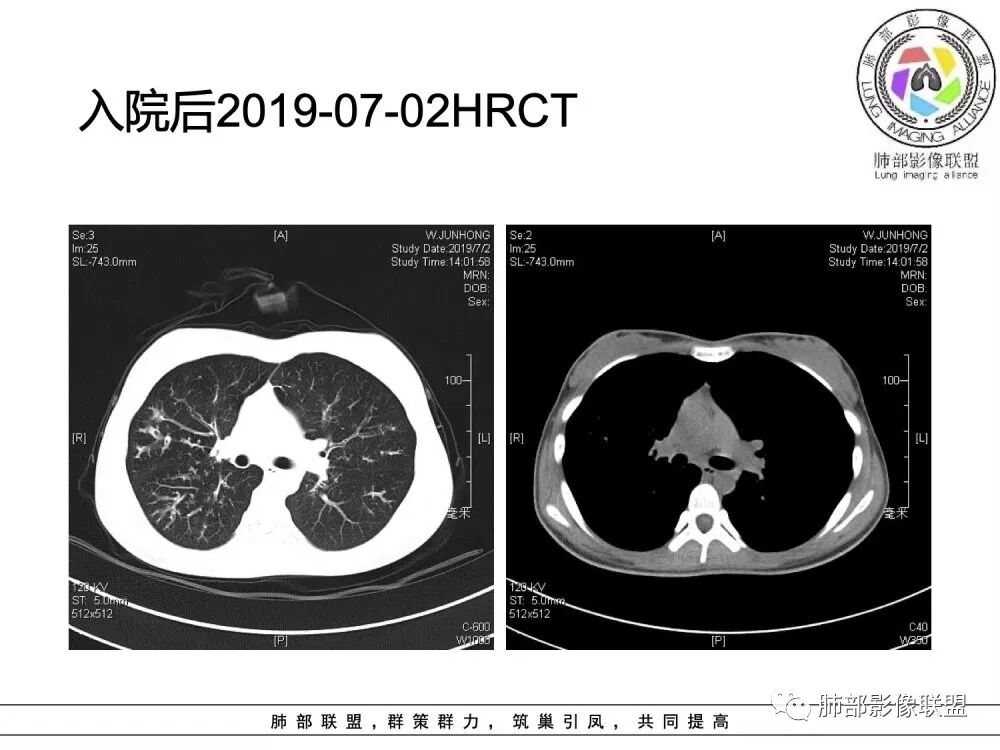

南边老师分析

这个病人15岁,病史10年,一直诊断支扩并感染,但是没提鼻窦病变;广泛支气管扩张,周围有伴随病灶,部分有钙化灶,肺气肿背景,首先是气道来源的病变,表现为:支气管壁增厚、支气管扩张、肺部感染;

(1)支气管壁增厚、支气管扩张

可广泛分布于两肺各叶,尤其是两肺上叶多见。支气管扩张主要是轻、中度柱状支气管扩张。支气管壁增厚既可发生于扩张的支气管,也可发生于非扩张的支气管,常为轻度增厚,管壁内外比较光滑。

(2)两肺弥漫性肺气肿

表现为肺野密度低而不均,在不同病例病变程度轻重不一,婴儿或儿童患者多见。

(3)支气管黏液栓

由于黏液分泌物潴留在气管内形成,依据黏液存留的支气管走向不同而形态各异,多呈圆形、椭圆形、管状或尖端指向肺门的“V”形或“Y”形高密度阴影,密度均匀,边缘光滑锐利,CT值一般为15±10HU,但存留较久的黏液栓CT值可高达40~80HU,增强扫描无强化。

(5)斑片状阴影

表现为感染性支气管肺炎和亚段肺不张。呈1~3cm大小不等的斑片状高密度影,上肺野常见或上肺野病灶分布较多。